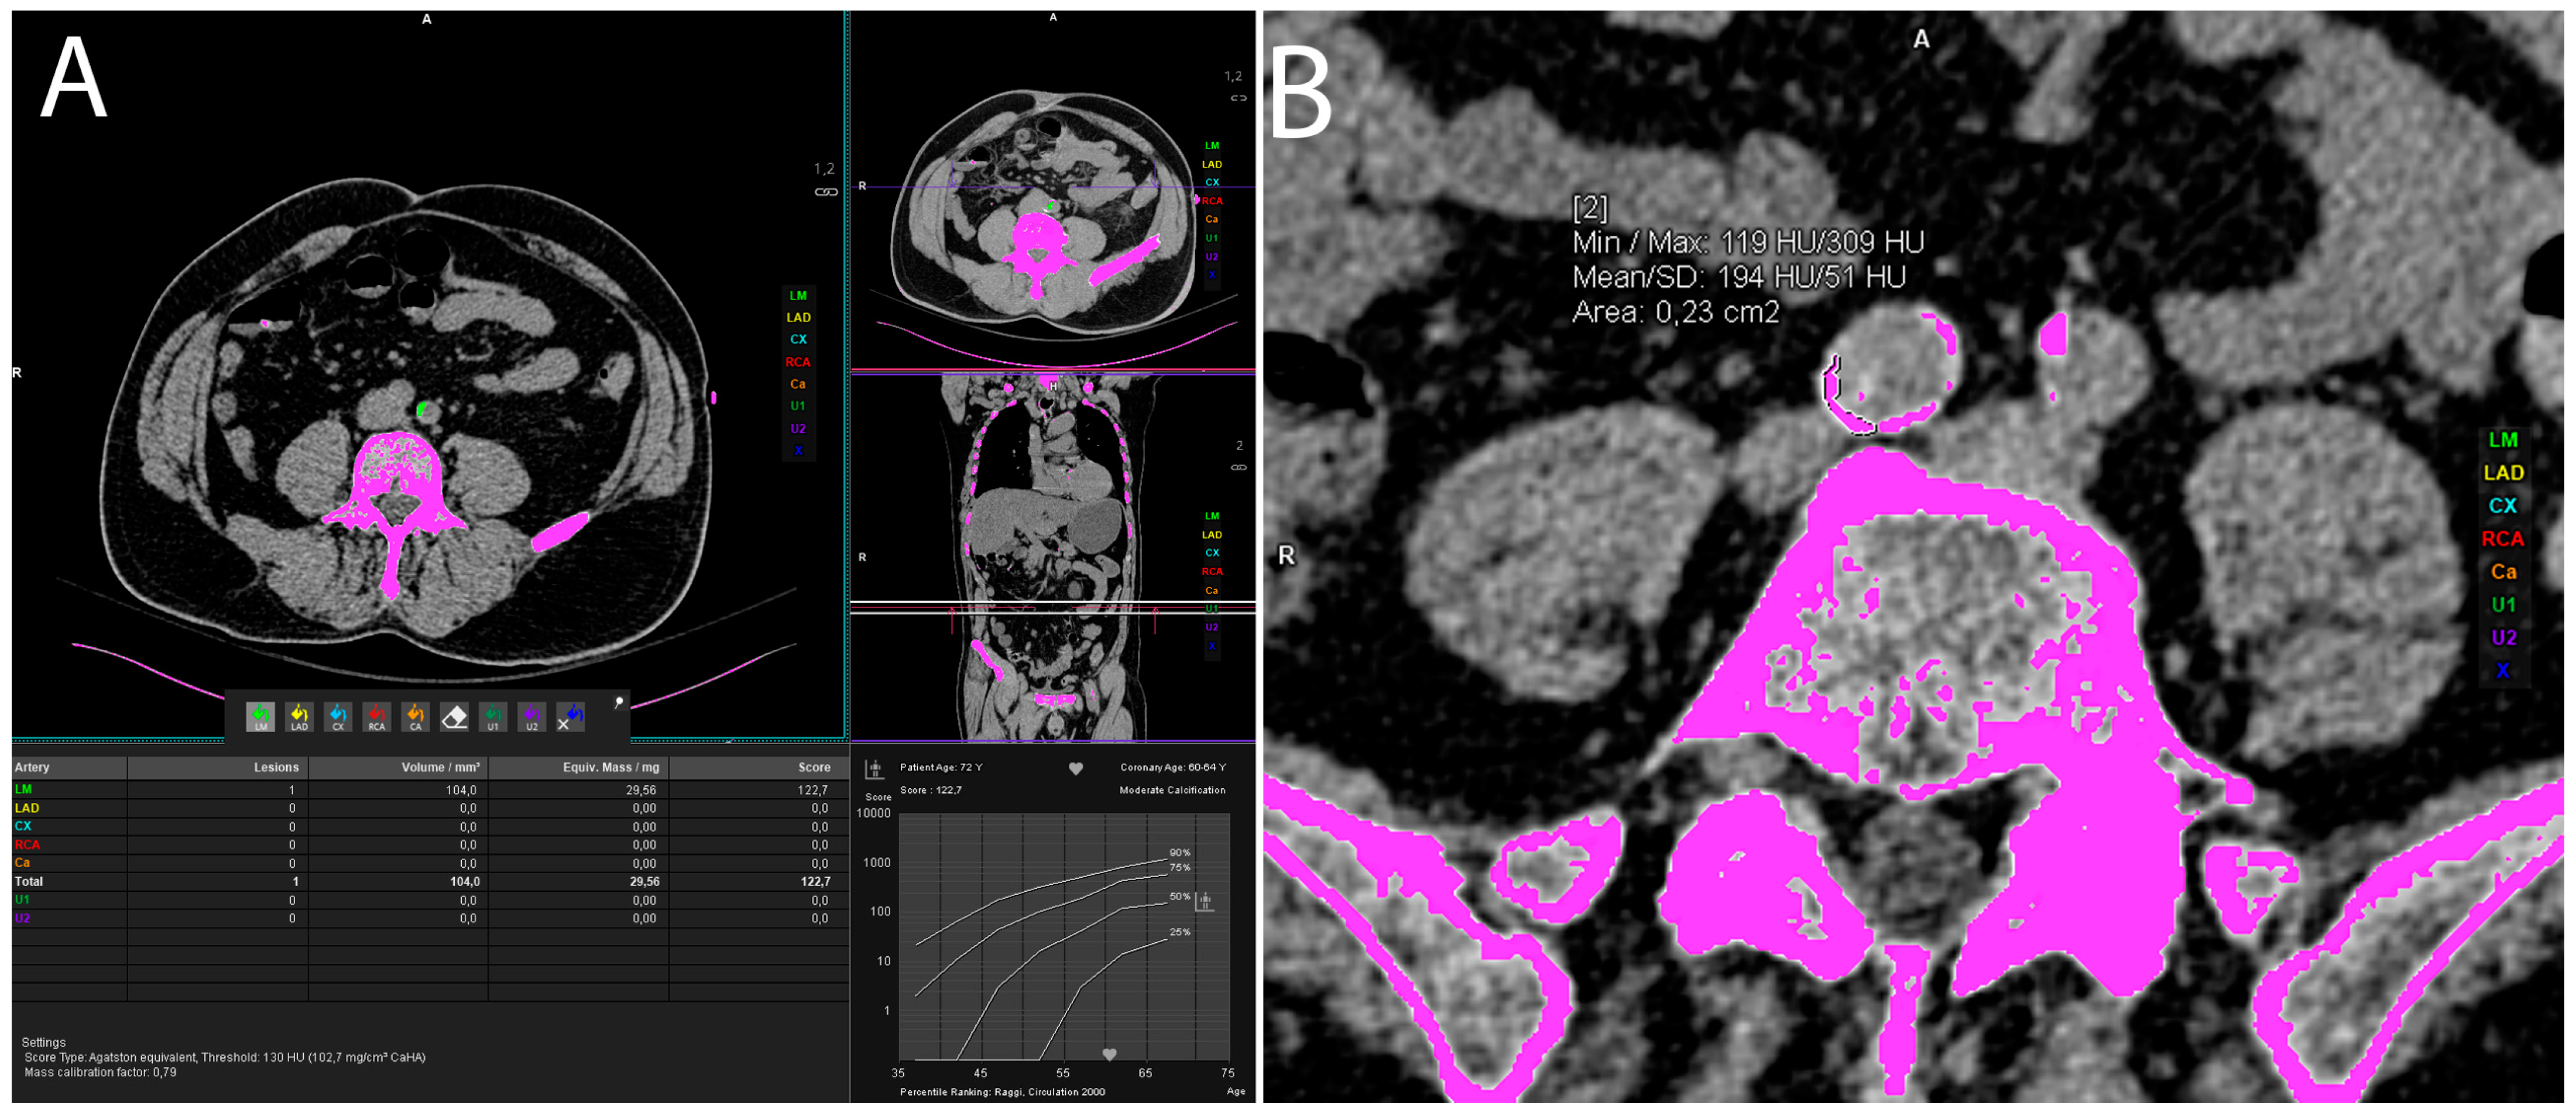

Figure 3. Representative axial CT images showing vascular calcification measurement by manually labeling every calcification in the artery of interest (A) or using freehand ROI method in case of larger calcifications (B).

2.5. Vascular Calcification Measurement

Volumes of arterial calcifications were measured using Siemens syngo.via VB60A_HF08 software “Ca Scoring” technique, which estimates calcifications on unenhanced CTs, and it is routinely used for coronary artery calcification measurement and calculation of the Agatston score. Each researcher underwent training prior to the measurements. The procedure was as follows: an unenhanced abdominopelvic CT scan was opened in the “Ca scoring” evaluation syngo.via VB60A_HF08 software. First, the coronary calcifications were manually delabeled and then each vascular calcification was manually labeled in the artery of interest. There were eight observed arteries: abdominal aorta, celiac trunk—celiac artery (CA), superior and inferior mesenteric artery (SMA and IMA), left and right common iliac artery (CIA), left and right external iliac artery (EIA) (Figure 3). If the vascular calcifications were too close to the bone structures (spine) or were extending into the adjacent artery (for example, the abdominal aorta to the iliac artery), the freehand ROIs were used to delineate calcifications of interest and calculate the calcification volume (Figure 3).